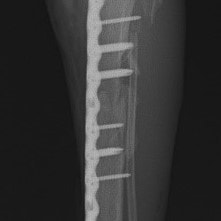

Advanced Locking plate system と Locking compression plate system

当院ではAdvanced Locking plate system(ALPS)と、Locking compression plate system(LCPS)という骨接合法で骨折症例の治療を行っています。

Advanced Locking Plate System

従来型のプレートのように広い面積で骨と接するプレートを用いて固定を行った場合、プレート下の骨はプレートとの接触面において血行が絶たれ壊死し、それがリモデリングされると骨密度が低下する。この骨密度の低下防ぐために、骨折部局所への血行を温存することの重要性が近年改めて認識されるようになってきている。Advaed Locking Plate System (ALPS)は従来型のプレートシステムの欠点を改良し、より使いやすく、より骨への血行を阻害しないようにというコンセプトで作られた。

Advanced Locking Plate System の特徴

- 骨への血行障害は最小限である

- 上下左右にベンディング可能でより3次元的な成形が可能

- すべての部位においてプレート強度は均一である

- ロッキングスクリューと圧着型スクリュー(皮質骨スクリュー)の双方が使用できる

- ダイナミックコンプレッション機能

- 生体親和性の高いチタン製

- トイ犬種から馬まで応用できるサイズ展開がある

トイプードル 右遠位橈尺骨短斜骨折のALPSによる内固定